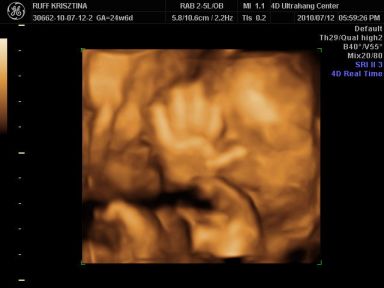

Kri: Brig nagyon cukorfalat a képeken, láccik jol érezte magát. Neked is medence fekvésű volt legutobb? Azt állitolag lehet a mozgásán is lehet érezni hogy merre van. Aztán kitudja...

Cherryke: nagyon édes a kis krapek !!

És neki é tök jol kivehető mindene, de olyan megtévesztő ilyenkor hogy kire hasonlit